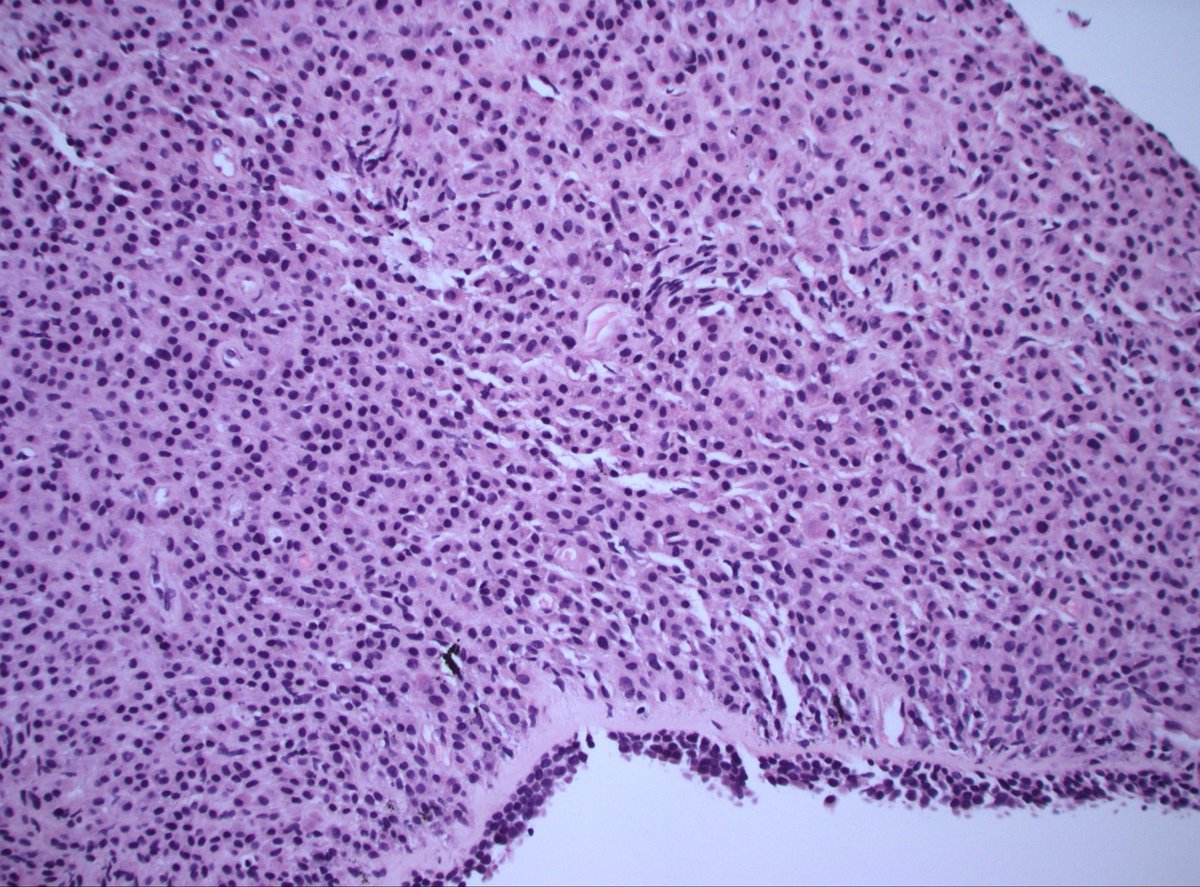

40 F. 10 cm deep thigh mass.

Answer ✅ youtu.be/QDb68_G1HR4?si…

Digital slide 🔬 kikoxp.com/posts/11800.

Differential dx: kikoxp.com/posts/12124

#BSTpath #pathologists #pathology #pathTwitter